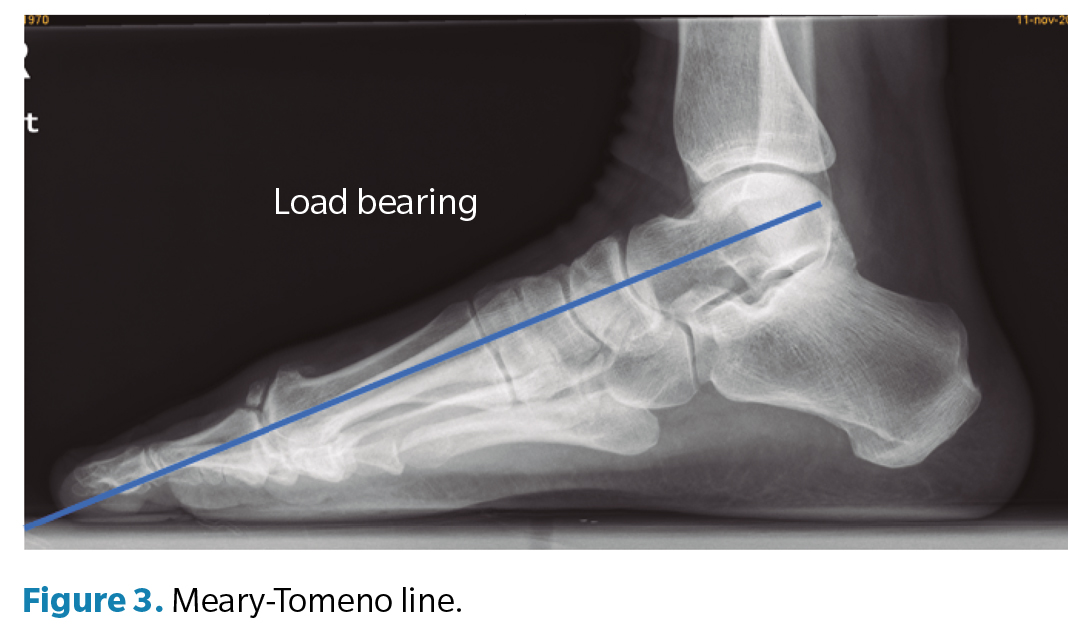

Regarding the goniometric variables in the lateral X-ray, the following angles were obtained: first metatarsal inclination angle, calcaneal inclination angle, Meary-Tomeno line, and internal Costa Bartani angle. The metatarsal inclination angle or Fick angle involves the inclination of the 5 metatarsals; however, for this study, only the inclination angle of the first metatarsal was considered (Figure 1), which was defined by the diaphyseal axis of the first metatarsal with the horizontal plane of the ground support11. The calcaneal inclination angle (Figure 2) is defined by the axis of the calcaneus, a line connecting the calcaneal tuberosity to the plantar margin of the anterior extension of the calcaneus near the calcaneocuboid joint, and the support plane (line formed by the proximal plantar tuberosity of the calcaneus and the head of the 5th metatarsal). A value of 20° is considered normal(12). The Meary-Tomeno line (Figure 3) is defined as the line passing through the axis of the talus (bisector of the angle formed by the tangent to the superior and inferior borders of the talus) and the axis of the diaphysis of the first metatarsal13). The internal Costa Bartani angle (Figure 4) is defined as the union of 3 points: the lowest point of the medial sesamoid, the lowest point of the posterior tuberosity of the calcaneus, and the lowest point of the talonavicular joint(14)..

These angles were chosen because they best represent the alignment of the internal longitudinal arch, in which the decrease or inclination towards the plantar side is associated with flattening of the arch(15).

The presence of joint space narrowing was associated with patients with a more plantar-vertex Meary-Tomeno angle (8.4° ± 5.6 vs. 1.1° ± 5.4), a smaller calcaneal inclination (21.4° ± 4.8 vs. 25.5° ± 6.4), and a smaller first metatarsal inclination (21.5° ± 2.5 vs. 23.8° ± 3.3) (p < 0.05) (Table 3).

Finally, based on the Coughlin and Shurnas classification, patients with any sign of hallux rigidus (n = 22; 60 %) showed a more plantar-vertex Meary-Tomeno line than those without signs of hallux rigidus (7.0° ± 7.0 vs. 2.7° ± 5.1 respectively; p = 0.041; CI [-8.301 to -0.183]) (Table 5).

The results of this study show that goniometric measures that represent values consistent with flattening of the medial longitudinal arch are associated with signs of joint degeneration of the 1MTPJ, with the Meary-Tomeno angle showing the best association with the clinical-radiographic diagnosis of HR.

Our results suggest that it is important to evaluate the position of the foot in a weight-bearing lateral X-ray to determine foot position, recommending the measurement of the Meary-Tomeno angle since the presence of a plantar vertex was associated with a higher presence of HR.

In conclusión, the results of the present study have shown that goniometric measures that represent values consistent with flattening of the MLA are associated with signs of joint degeneration of the 1MTPJ, with the Meary-Tomeno angle showing the best association with the clinical-radiographic diagnosis of HR, suggesting a possible association between HR and tarsal pronation or flatfoot.